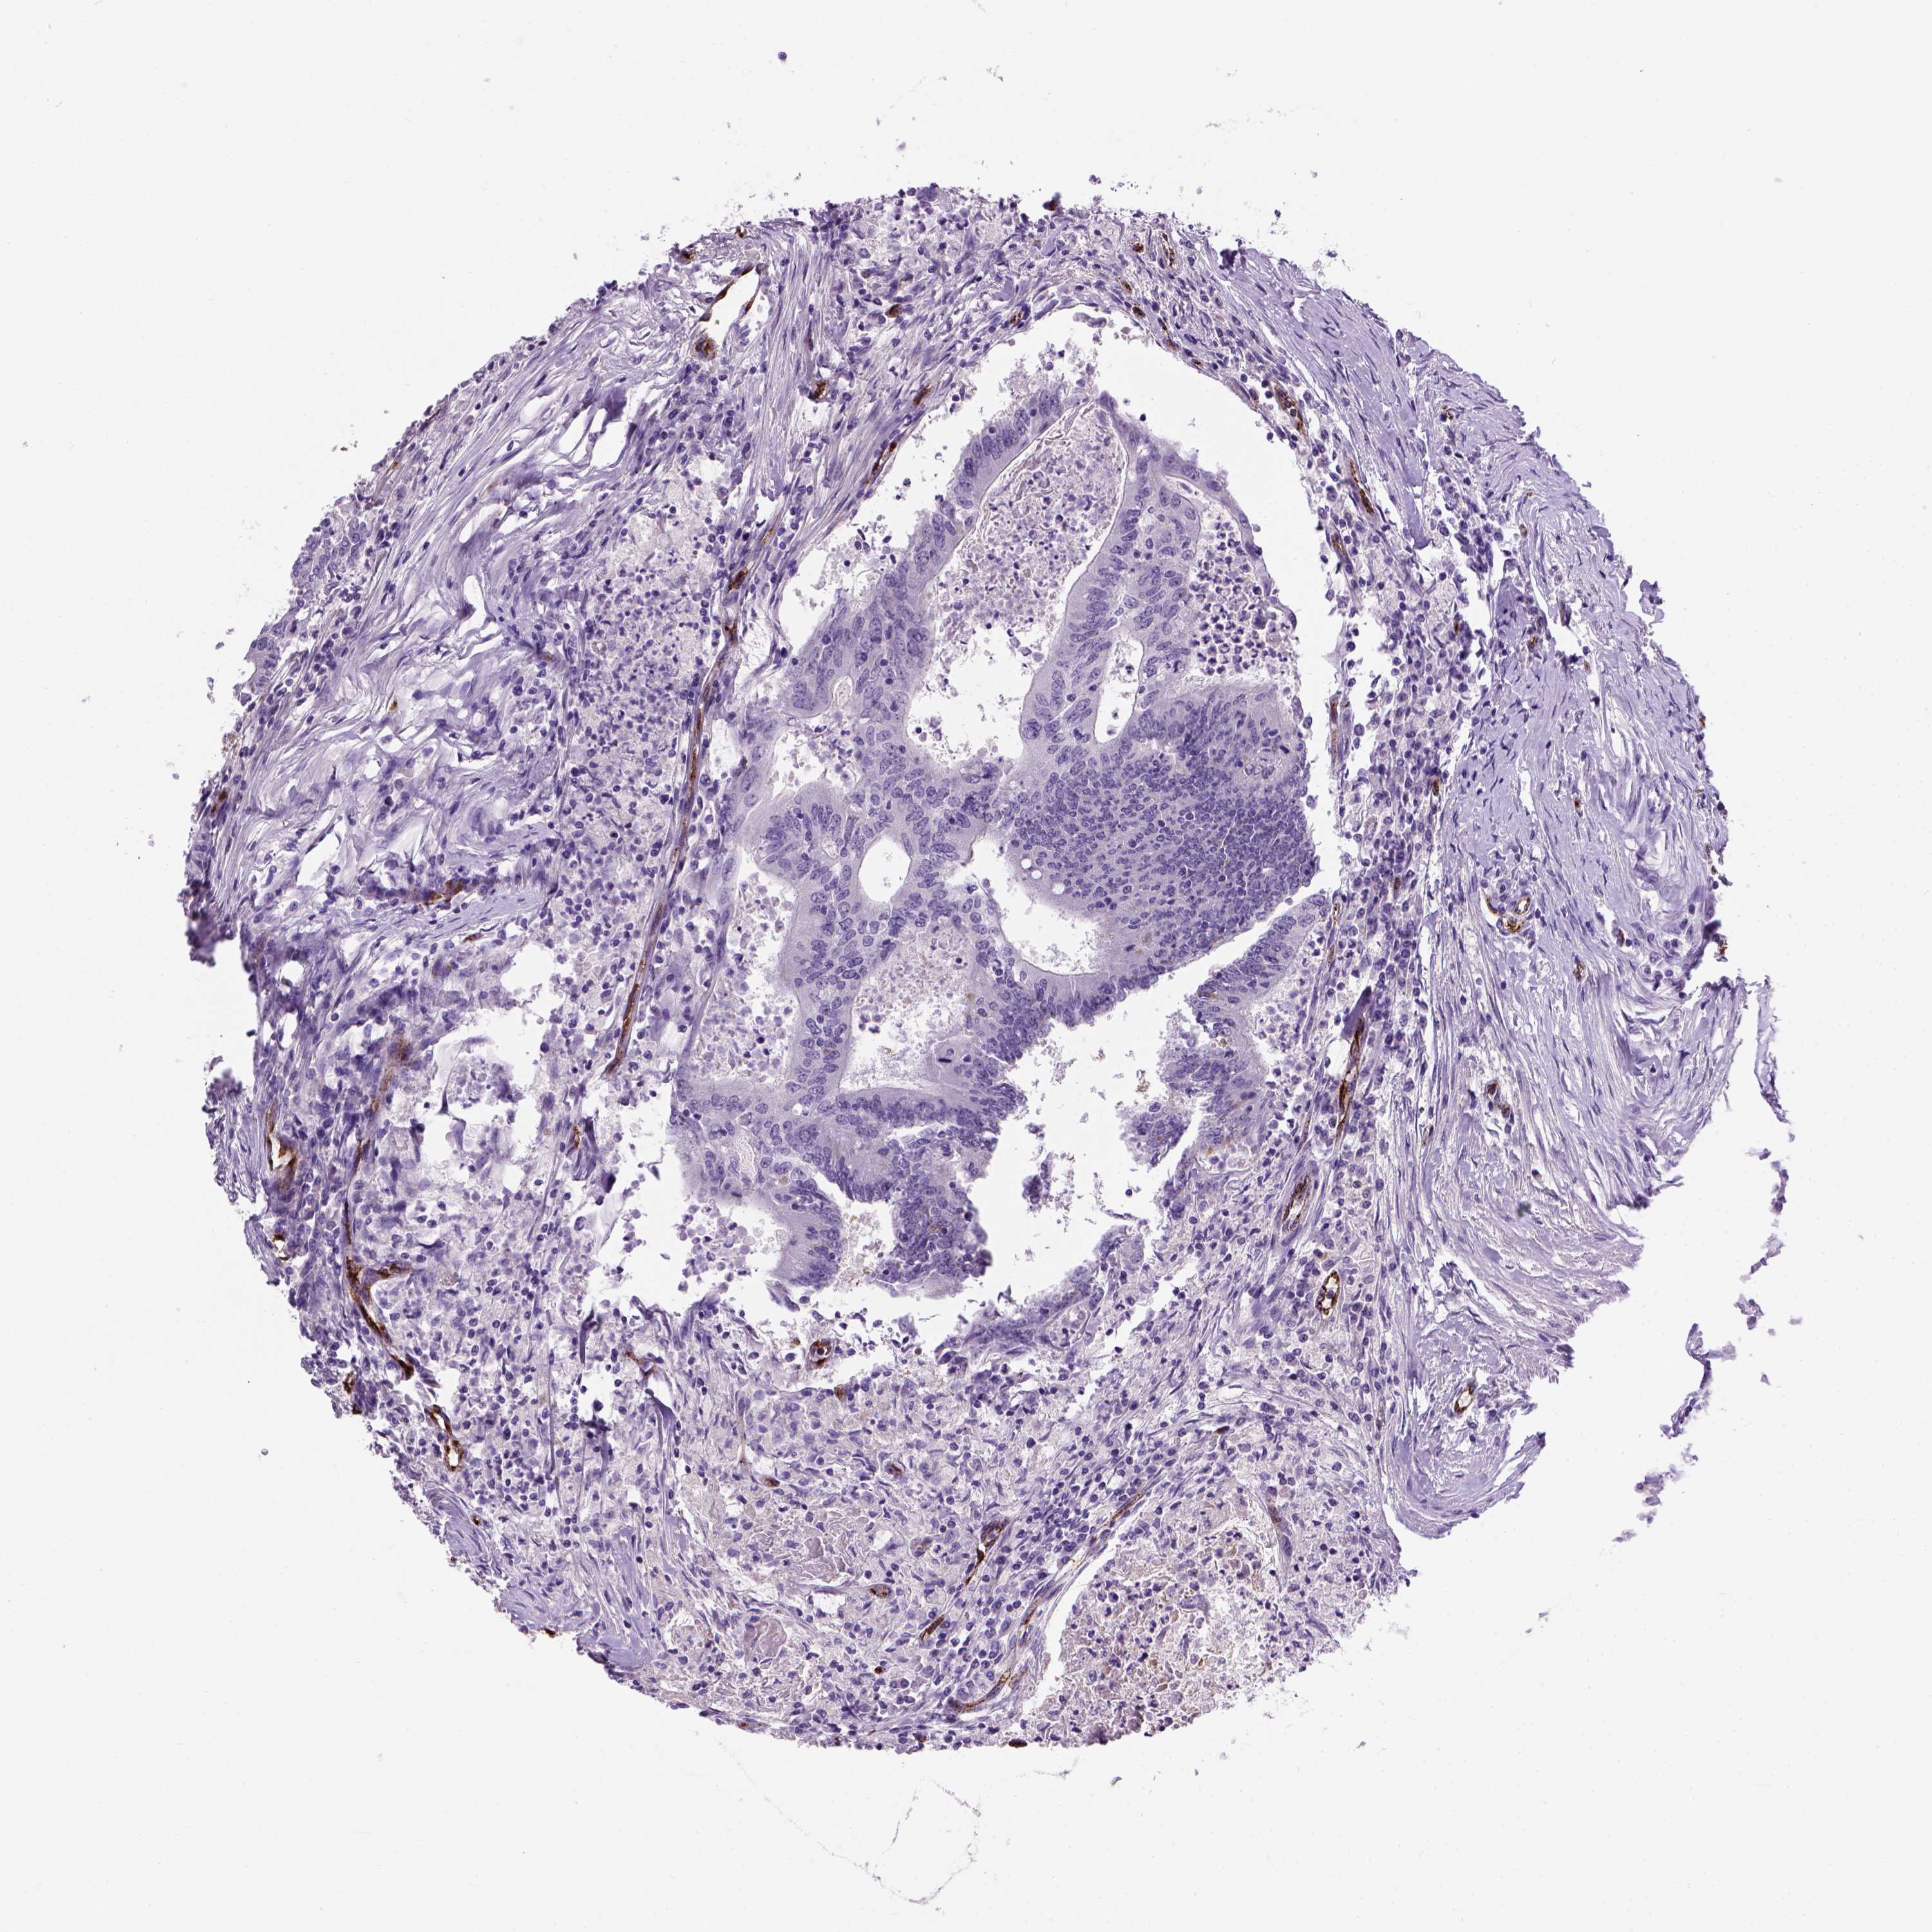

CANCER COLORECTAL CANCER Show tissue menu

ANTIBODIES

AND

VALIDATION